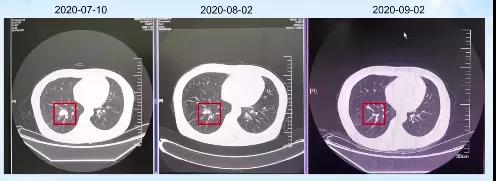

2020-08-02患者因需进行第二次化疗住院,检查发现患者各项肿瘤指标明显下降,肺部肿瘤组织明显缩小,体格检查较之前也有明显好转,疗效评估部分缓解(PR)。

2020-09-02患者因需进行第三次化疗住院。患者乏力症状虽然比治疗前好转,但是较第二次住院时并没有改善,同时头晕症状依旧明显。不过患者的神经系统还是有改善的,肿瘤相关指标也持续降低,胸部CT提示患者肿瘤组织进一步缩小,疗效评估PR。

2020-10-26因患者需进行第四次化疗再次住院,患者头晕、乏力症状仍时有发生,但是各项体格检查以及神经状态还算正常。肿瘤指标稳定,胸部CT显示病灶依旧缩小,疗效评估PR。